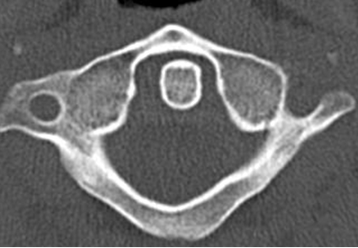

Fig 192. Odontoides normal.

TAC axial. Relación normal entre la odontoides y el arco anterior de C1.